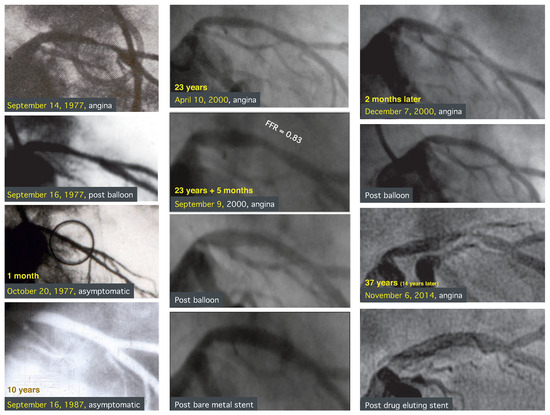

Percutaneous Coronary Intervention, Not All Roads Lead to Rome

by Bernhard Meier

Cardiovasc. Med. 2015, 18(10), 267; https://doi.org/10.4414/cvm.2015.00364 - 21 Oct 2015

Percutaneous coronary intervention (PCI) started with a first patient in Zurich, Switzerland, treated by Andreas Grüntzig on September 16, 1977. Having been part of that intervention, I enjoy the privilege of taking care of this patient since. He is still enjoying excellent health [...] Read more.

Percutaneous coronary intervention (PCI) started with a first patient in Zurich, Switzerland, treated by Andreas Grüntzig on September 16, 1977. Having been part of that intervention, I enjoy the privilege of taking care of this patient since. He is still enjoying excellent health and needed only two additional percutaneous interventions in his coronary arteries after 23 and 37 years, respectively. PCI saw an unprecedented evolution to today’s role as the most common major medical intervention around the globe. As is typical for a success story, many people have been co-builders. Even more people have tried to contribute to PCI or even replace it with modifications or alternatives that do not benefit patients. This was not always recognised immediately but the only real breakthrough, the coronary stent, was finally recognised by all as the only necessary adjunct to the initial balloon. The achieved degree of perfection of PCI will make it hard, if not impossible, to improve upon it by a change of paradigm, while small adaptations will continue to be introduced because they do not need randomised trials for approval. Full article

Show Figures

Graphical abstract